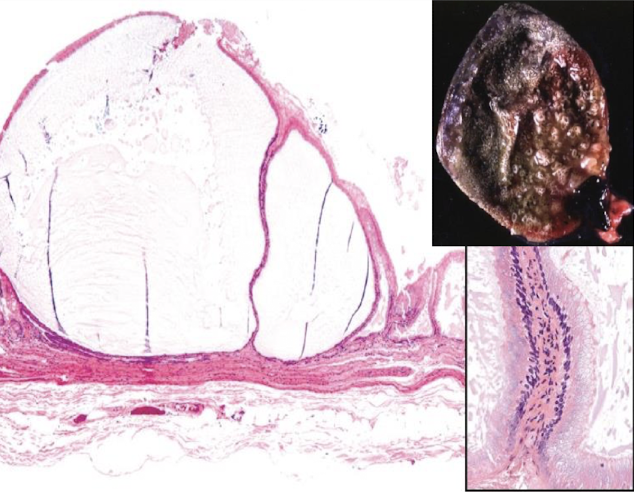

What is a gallbladder mucocoele?

abnormal accumulation of thick, inspissated mucus w/in gallbladder → gallbladder markedly distended & filled w/ immobile bile & mucus

What is the clinical significance of gallbladder mucocoeles?

abdominal pain, biliary obstruction, risk of rupture, bile peritonitis

clnically significant & potentially life-threatening

What is cystic mucinous hyperplasia?

benign proliferative lesion of gallbladder mucosa, characterized by mucin filled epithelial cysts